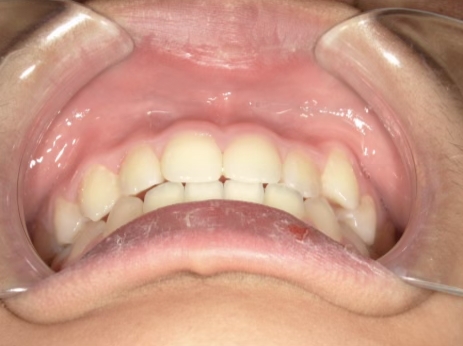

治療中⑨ 中3:14y4m

モノブロック装置で左上八重歯が改善しました

今後、必要によりマルチブラケット法へ移行予定です